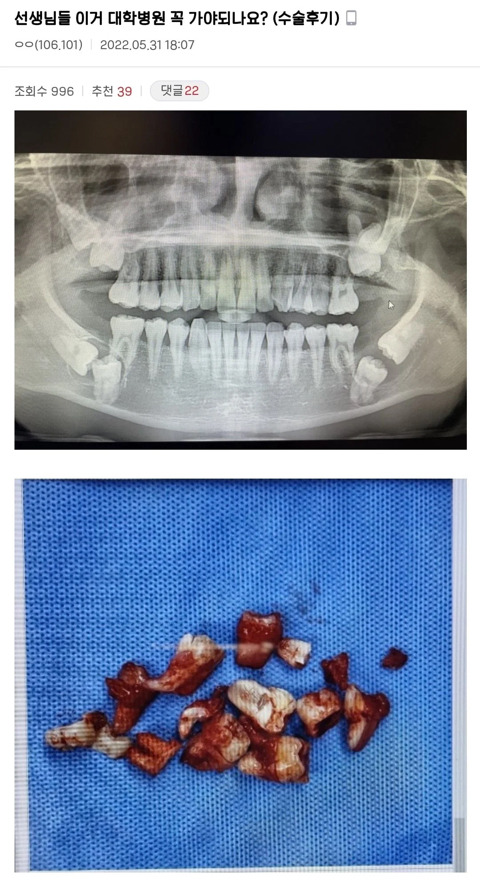

• 작성자그래요내가바로로또1등이에요 | 작성시간 2시간 54분 전 new 4개 다 뽑았는데… 마지막 사랑니가 신경에 가까워서 그거 뽑고 좀 많이 고생함. 부어올랐지만 잇몸을 뚫고 나오지는 않아서 염증 긁으러 갔는데 그냥 빼도 된다고 해서 잇몸 가르고 뺌. 사진상 신경에 가까워 보이는데 만약 신경이랑 붙어있으면 좀 어럅다 그랬나. 근데 붙은 건 아니고 가까워서 빼긴 뺏는데 마취 풀리자마자 아파뒤지는 줄. 옛날에는 신경질이 났다면 진짜 아파서…. 거의 세 달간 아픈 느낌에 생리통이랑 치통 같이 오고 잇몸 약해진 느낌에 찬 거 먹는 것도 부담이었음

• 답댓글 작성자그래요내가바로로또1등이에요 | 작성시간 2시간 52분 전 new 경험상 위에는 수월했고 아래 두 개가 힘겨웠음. 다른 쪽은 얘가 발이 달린 건지 한쪽 뿌리만 휘어져 있어서 치과의사가 고생 좀 했어 ㅋㅋ 근데 진짜 4개 다 마취할 때가 제일 아픔 ㄷㄷ